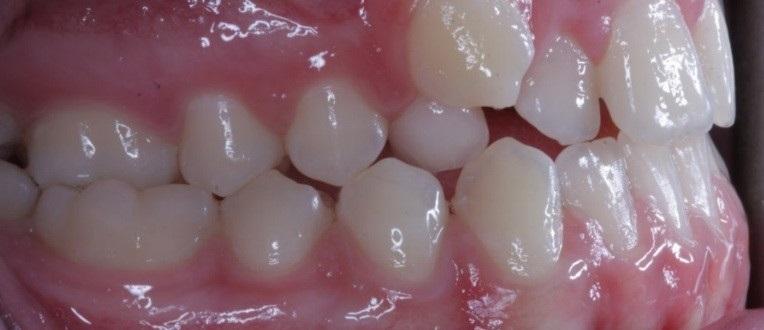

Molar crossbite is when the upper teeth or jaw are narrower than the bottom teeth and when they bite down the top teeth sit down inside the bottom back teeth. This is particularly a problem if it causes the lower jaw to shift sideways when the teeth close together.